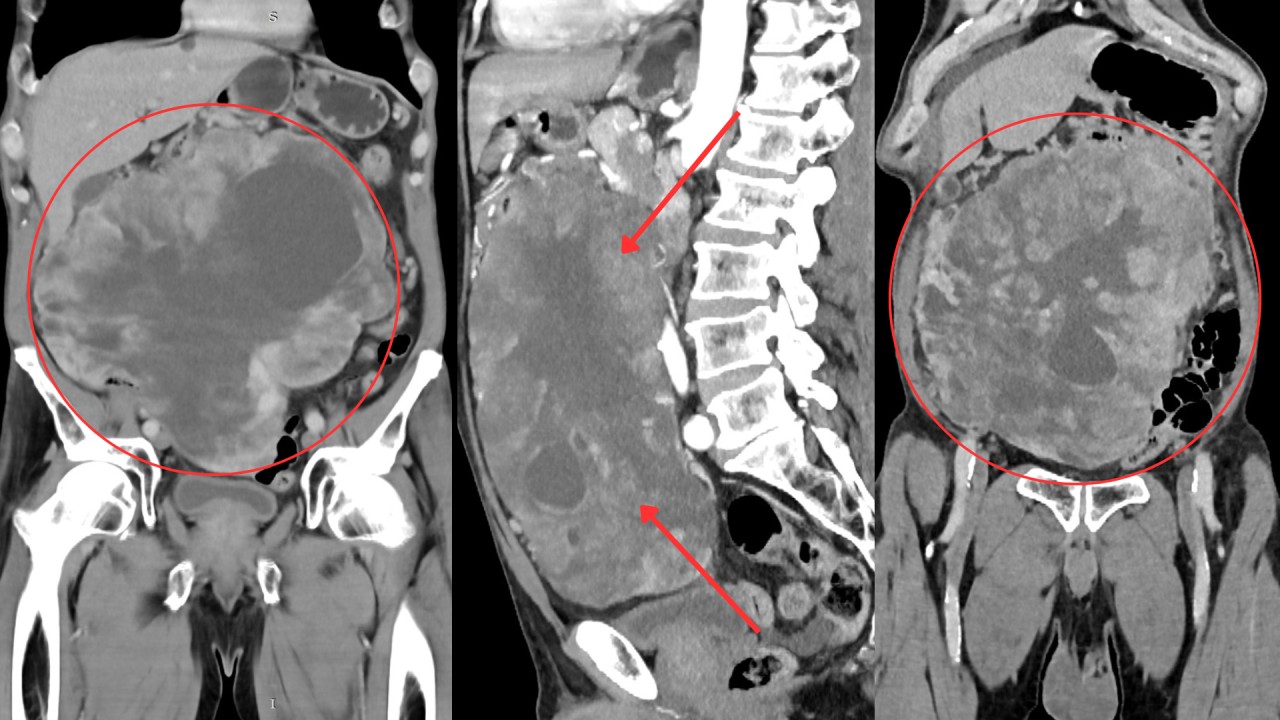

Կլինիկական բացառիկ դեպք. որովայնի խոռոչի հսկա մետաստատիկ ուռուցքը ամբողջությամբ հեռացվել է